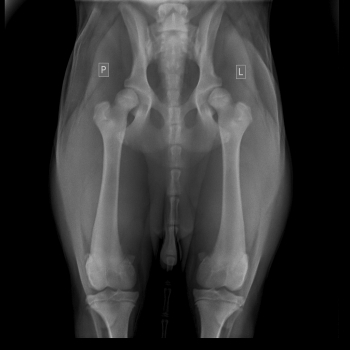

Badaniem można stwierdzić bolesność podczas biernych ruchów w stawie, mniejszy zakres ruchu w stawie, fenomen Ortolaniego – charakterystyczne „klikniecie” w stawie biodrowym wynikające z jego niestabilności. Najdokładniejszym badaniem jest badanie radiologiczne stawów biodrowych. Zdjęcie wykonuję się w projekcji grzbietowo-brzusznej – V-D, pies leży na grzbiecie (niekiedy konieczne jest wykonanie dodatkowych zdjęć w innych projekcjach). W większości przypadków do wykonania takiego zdjęcia konieczne jest uspokojenie pacjenta – sedacja i rozluźnienie mięśni – miorelaksacja, co uzyskuję się za pomocą iniekcyjnych środków farmakologicznych.

Objawy radiologiczne są różne w zależności od stopnia nasilenia zmian w stawie, dotyczyć mogą panewki stawu biodrowego, główki kości udowej lub obu struktur jednocześnie.

Do określenia stopnia dysplazji stosuje się następującą skalę ocen:

A - stawy biodrowe normalne

B - Stawy biodrowe prawie normalne

C - dysplazja nieznaczna

D - dysplazja częściowa (ograniczona)

E - dysplazja ciężka